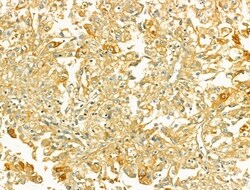

Invitrogen™ TOMM40 Polyclonal Antibody

Antibody detects endogenous levels of total TOM40.

| Immunohistochemistry (Paraffin), Western Blot | |

| A synthesized peptide derived from human TOMM40(Accession O96008), corresponding to amino acid residues R173-Q223. | |